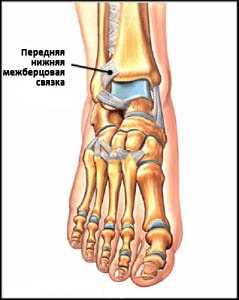

Голеностопный сустав образован сочленением таранной кости с малоберцовой и большеберцовой костями, удерживаемыми посредством межкостной мембраны, а также межберцовыми (задней и передней) связками. При этом, таранная кость, показанная на рисунке 2, размещается в образованной двумя берцовыми костями U-образной «вилке».

Рис. 2 Таранная кость (Т) размещена в U-образной «вилке». Межберцовый дистальный синдесмоз, образованный сочленением малоберцовой (Fib) и большеберцовой (Tib) костей и стабилизирующийся благодаря синдесмозным связкам (отмечены красным цветом), отвечает за нормальное функционирование голеностопа.

Передняя нижняя межберцовая связка (далее ПНМС), отвечающая за стабилизацию U-образной «вилки» берцовых костей, подвергается травмированию в случае ротации зафиксированной на той или иной поверхности стопы. Зачастую, образующийся после заживления данного вида связки рубец, может спровоцировать развитие импинджмента.

Рис. 5 Анатомия ПНМС